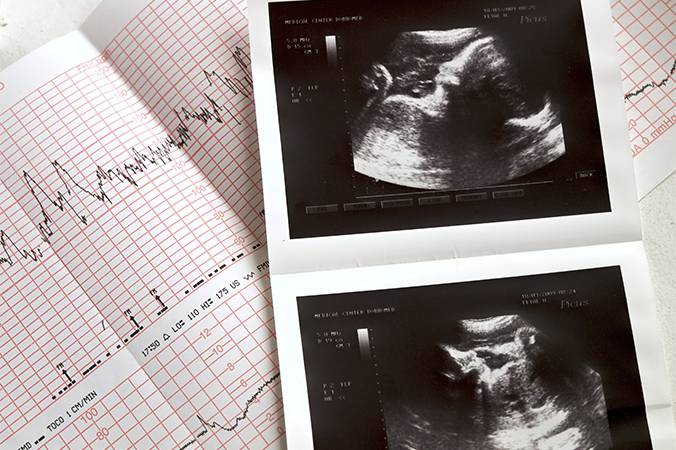

O ecocardiograma fetal é um exame essencial para a avaliação da saúde do coração do bebê ainda no útero. Rápido, indolor e seguro para a mãe e o feto, o procedimento fornece imagens detalhadas do órgão em formação, permitindo ao profissional identificar possíveis alterações nas válvulas cardíacas, músculos e fluxo sanguíneo.